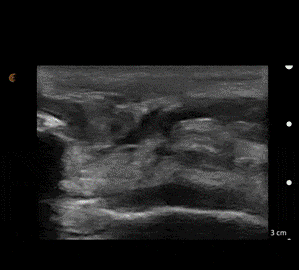

The nurse immediately gets an IV started, and you give him 50 mcg IV fentanyl. He goes to x-ray, which shows no fracture or dislocation, but does reveal a high-riding patella. You grab your ultrasound and immediately notice a defect in the patellar tendon (See Figure 3).

Figure 3- Patellar tendon rupture

The diagnosis of patellar and quadriceps tendon rupture can be made clinically, based on history and exam findings alone. However, x-rays should be obtained as patellar, and quadriceps tendon ruptures can be associated with avulsion fractures of the patella. You may also see a low riding patella (patella baja) with a quadriceps tendon rupture or a high riding patella (patella alta) with a patellar tendon rupture, which can help make the diagnosis. Ultrasound is the best confirmatory test in the ED, as it allows the clinician to determine the presence and size of muscle and tendon rupture and to view the muscle and tendon function dynamically to assess for gaping with motion or mild resistance.